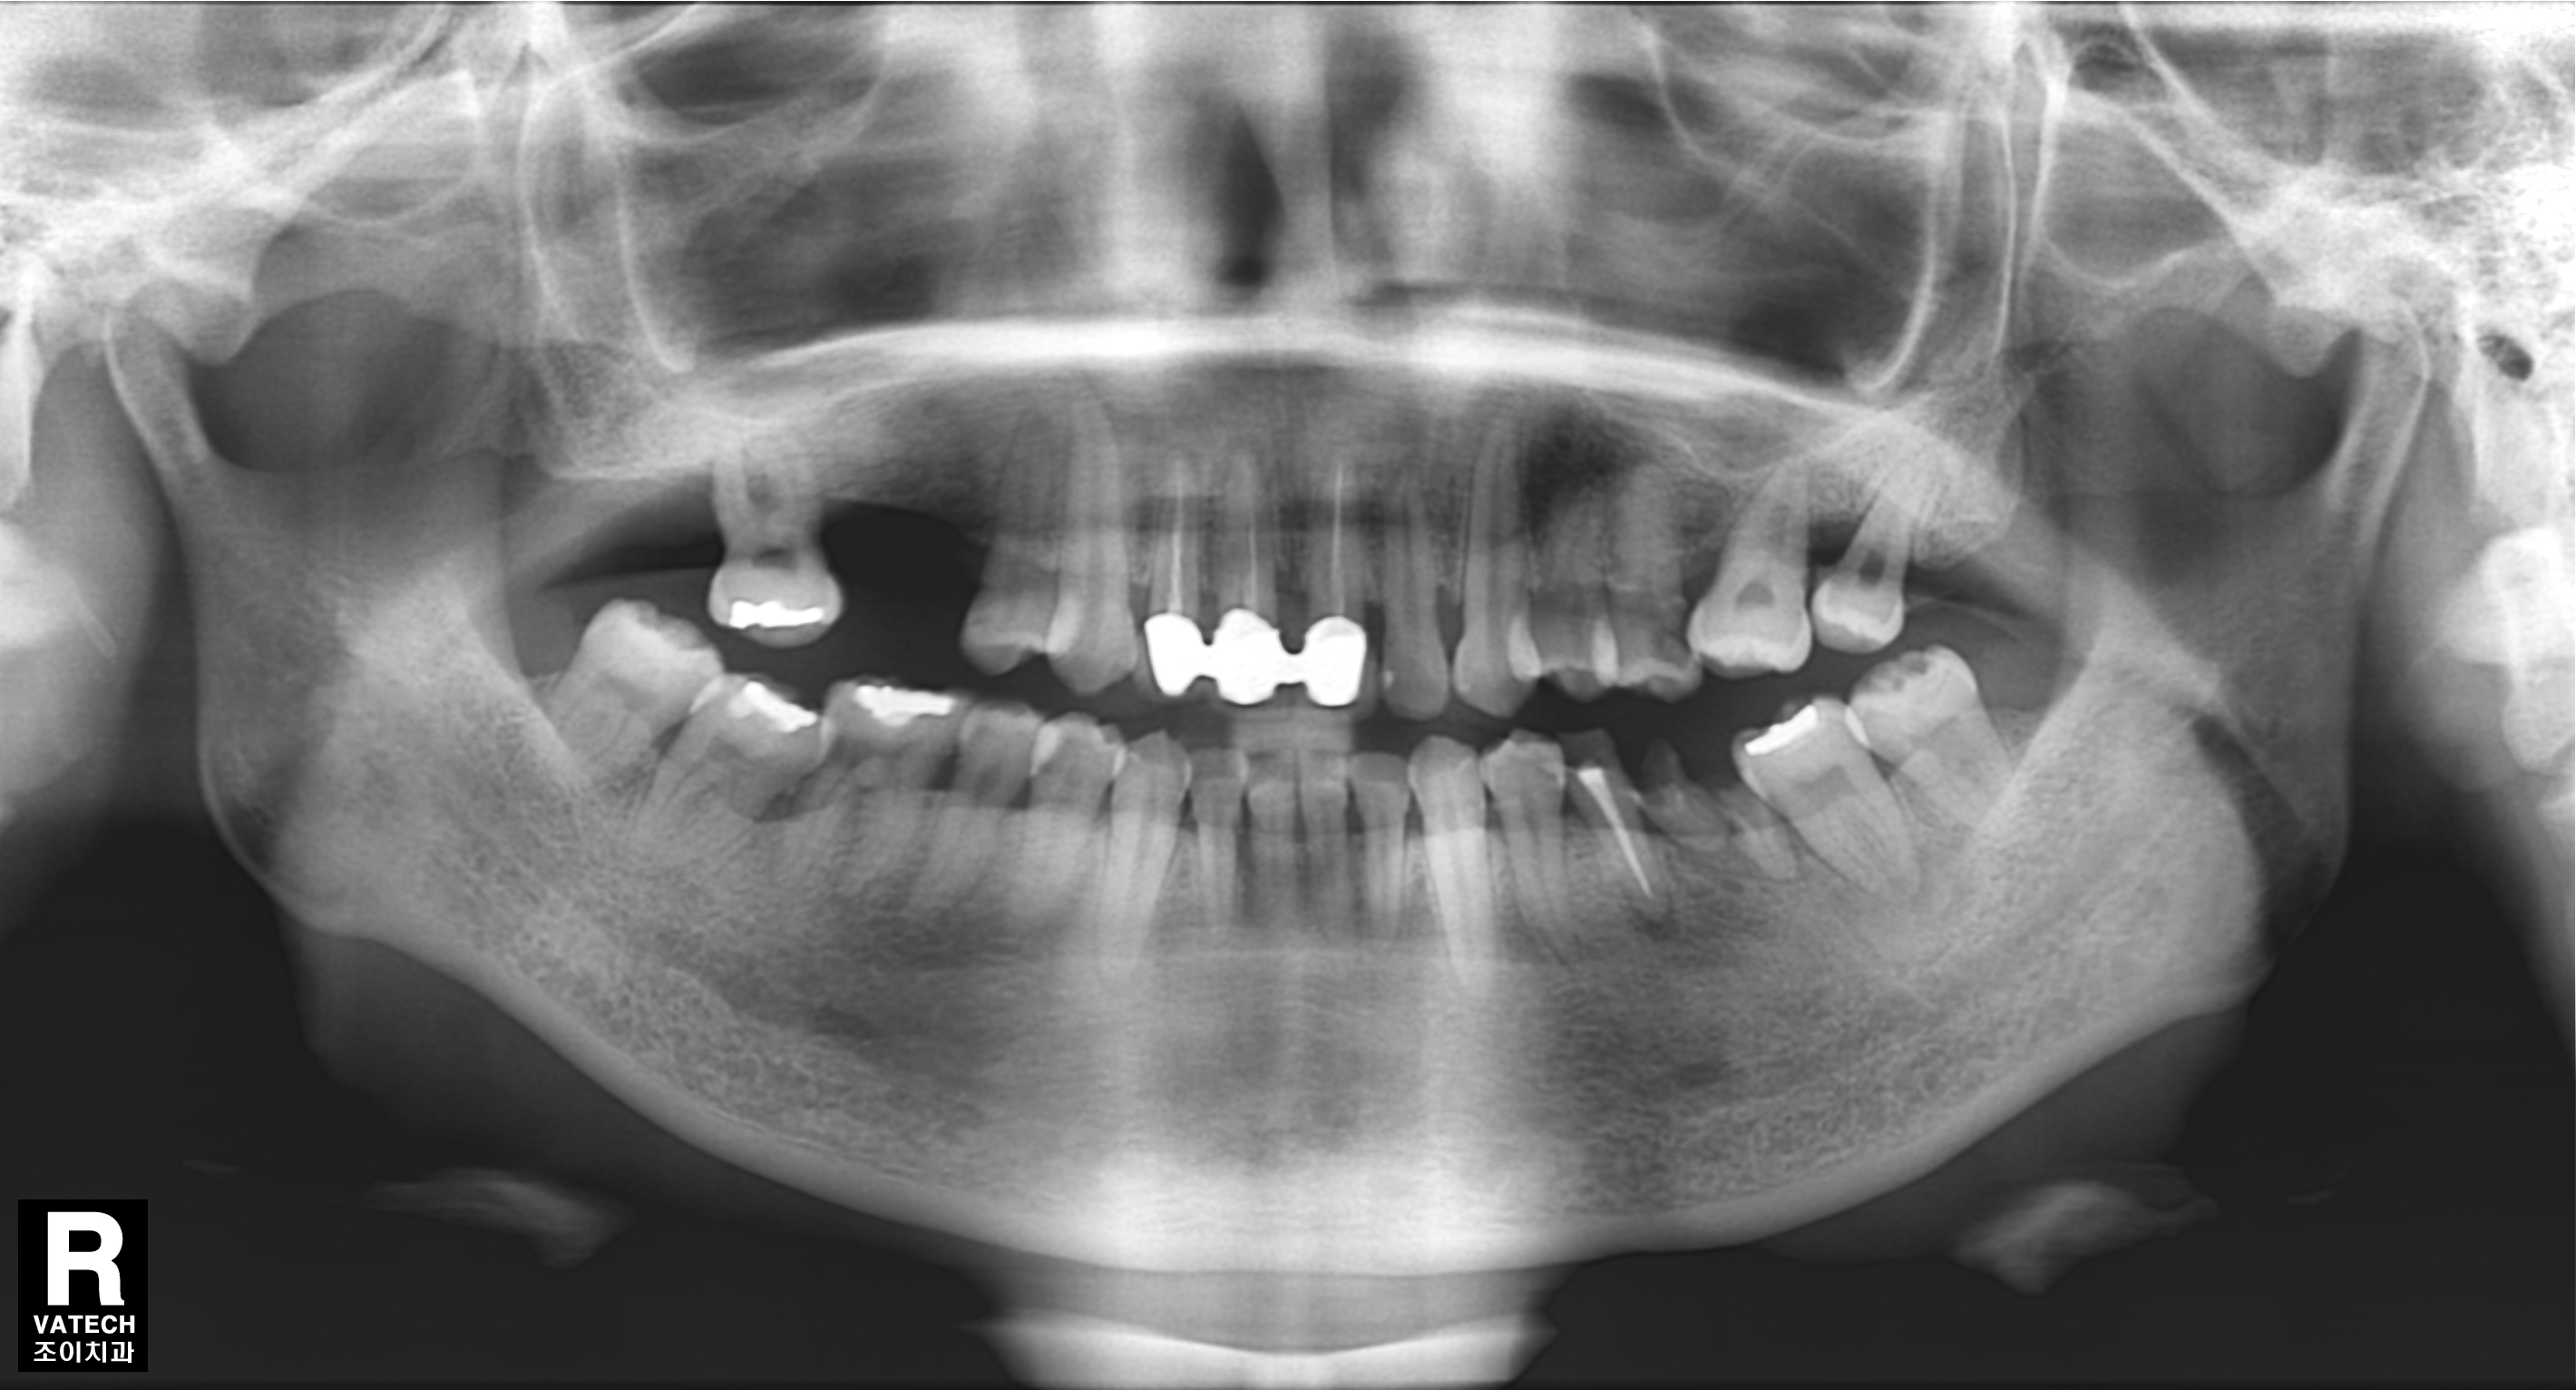

[임플란트] 제목 : 충치 및 치주질환 임플란트

충치와 치주질환에 의한 치아상실로 임플란트 치료함.